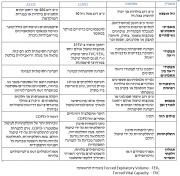

| 16:37, 7 במרץ 2015 | Gold table3.jpg (קובץ) |  |

233 קילו־בייטים | Motyk | 1 | |

| 16:35, 7 במרץ 2015 | Gold table2.jpg (קובץ) |  |

210 קילו־בייטים | Motyk | 1 | |

| 16:32, 7 במרץ 2015 | Gold table1.jpg (קובץ) |  |

373 קילו־בייטים | Motyk | 1 | |